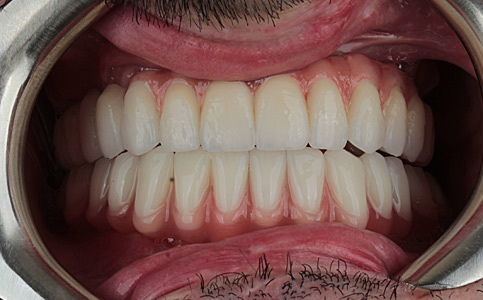

Dzięki koronom pełnoceramicznym w szczęce i żuchwie oraz uzupełnieniu braków zębowych implantami, pacjentka może znów się szeroko i pięknie uśmiechać.

Zobacz efekty przeciągając suwak w prawo lub w lewo.